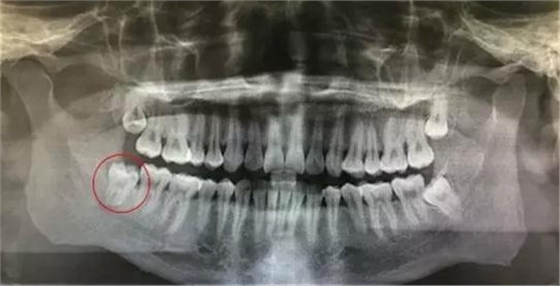

圖2.局部放大的影像學(xué)檢查:48雙根環(huán)抱型,遠(yuǎn)中有牙囊影。